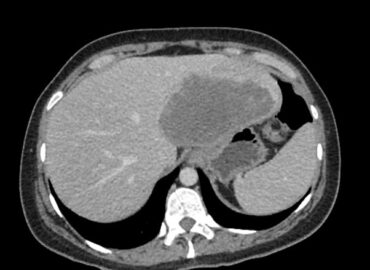

Mujer de 41 años con fiebre sin foco

Mujer, 32 años, dolor abdominal